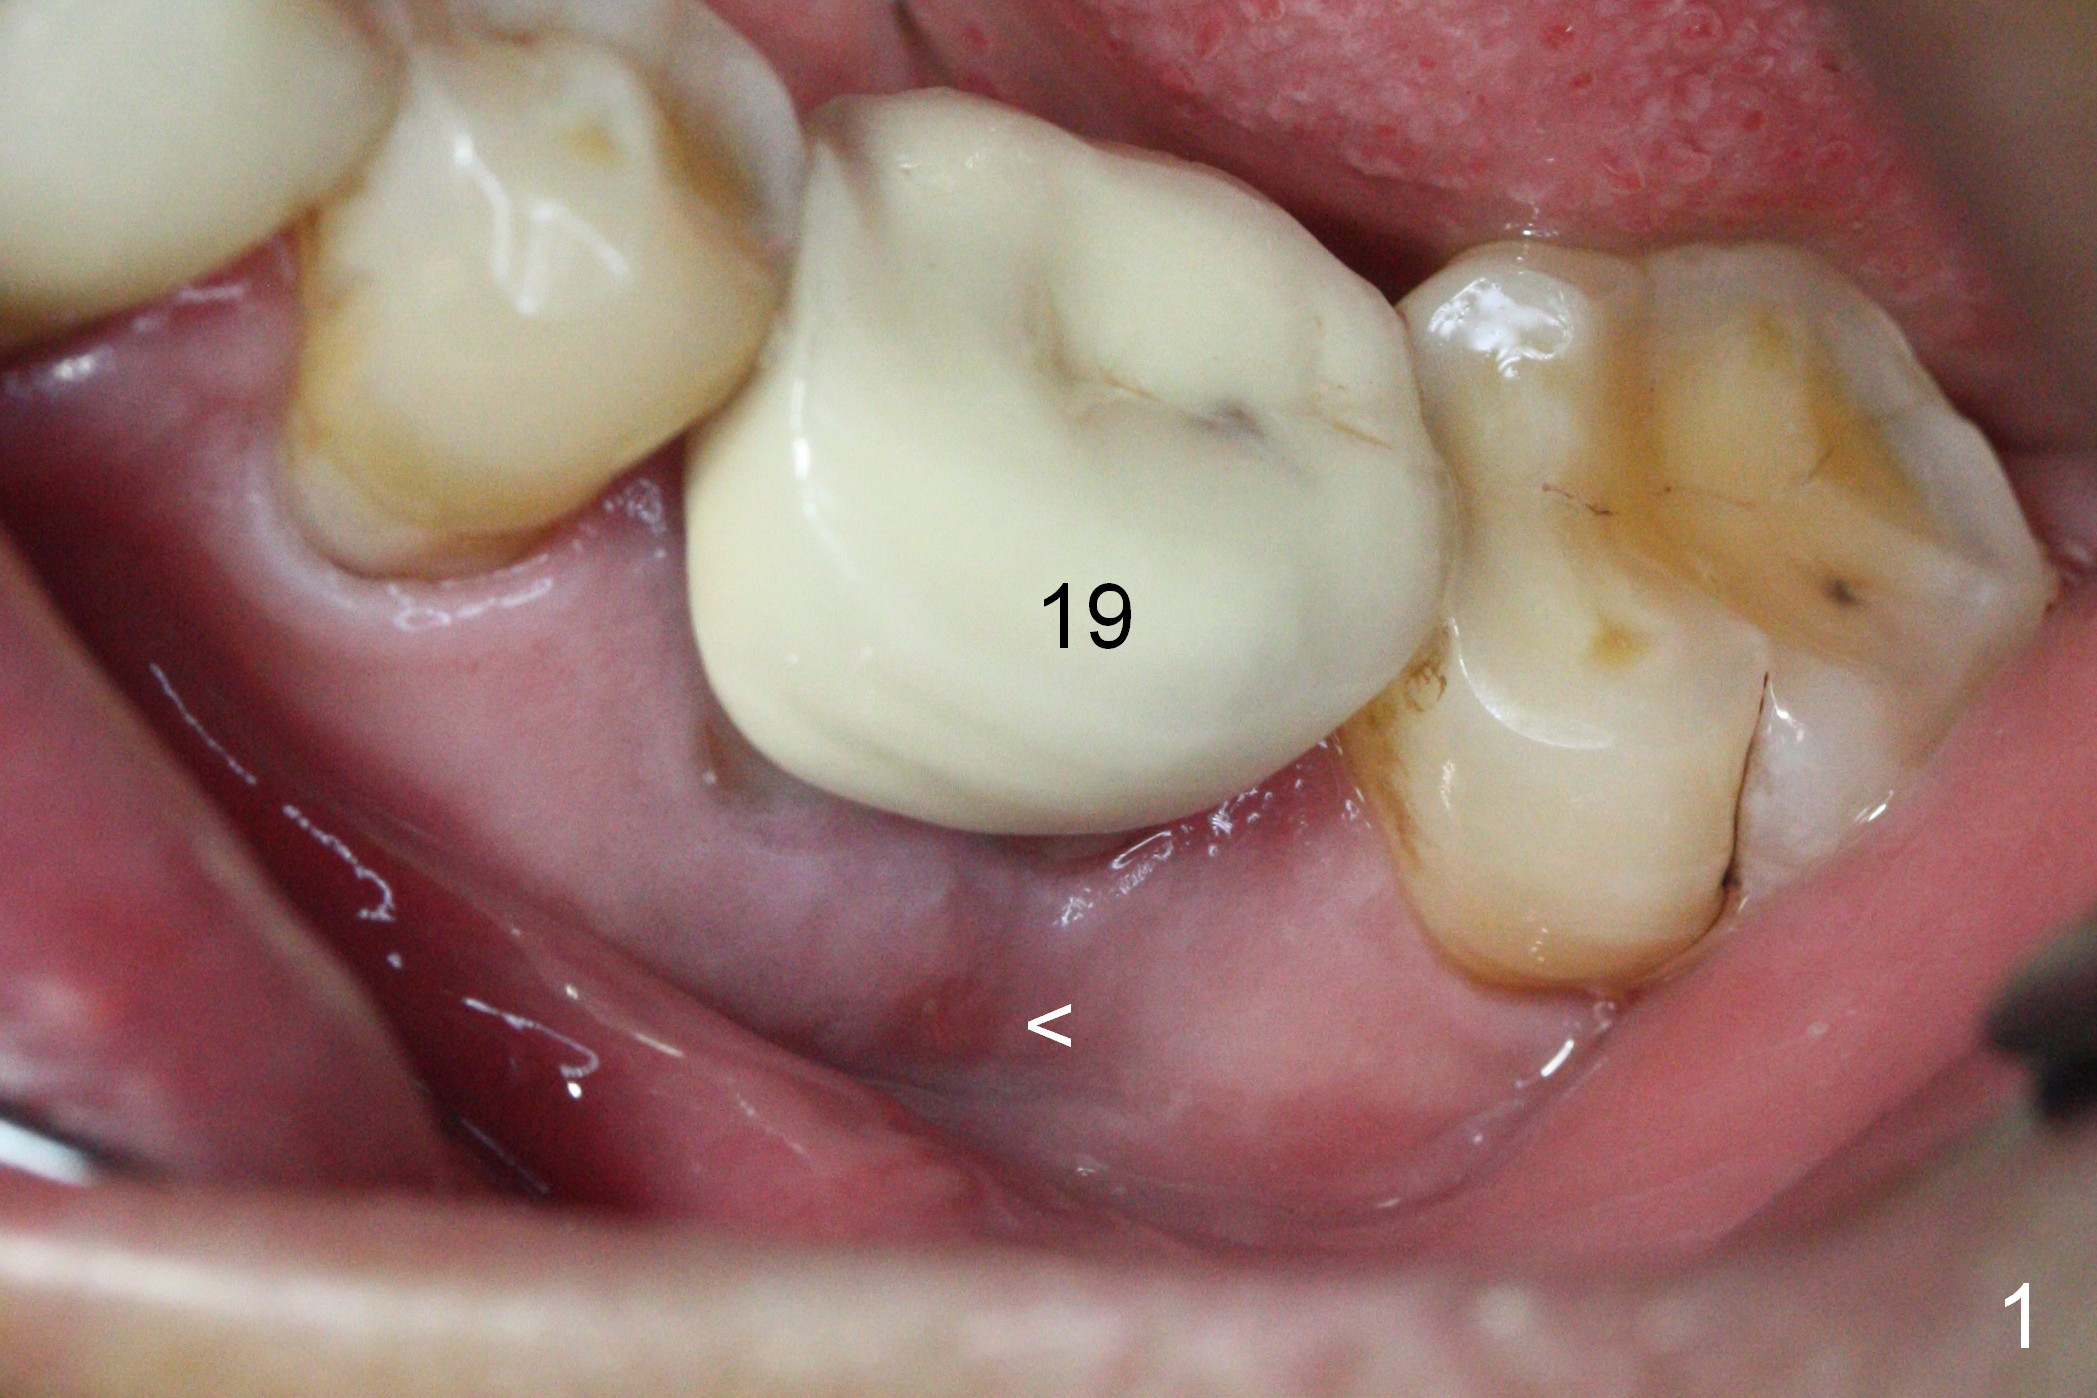

The asymptomatic tooth (#19) has a midbuccal fistula (Fig.1 <). The mesiobuccal pocket is 10 mm with purulent discharge from the sulcus (Fig.2,3). The mesiobuccal wall defect is confirmed when the tooth is extracted. Osteotomy is initiated lingually in the septum following septal crestoplasty (flattening) (Fig.4: using 1.6 mm drill for 9 mm). Since the lingual portion of the osteotomy is higher, it is difficult to use drill with stopper. For the narrow septum osteotomy, multiple drills are used sequentially (Fig.5 after 4.3 mm drill). A 4.5x11 mm dummy implant is placed (Fig.6) apparently too deep. When a 5x11 mm IBS implant is being placed, the depth is tightly controlled (Fig.7). The implant is apical to the lingual crest, whereas there is ~ 2 mm implant exposure buccally. That is, there is a large gap mesiobuccally (Fig.8), which is filled with .5-1.5 mm allograft (Fig.9 *). A 6.5x5.7(3) mm abutment (A) is placed and trimmed for an immediate provisional (Fig.10 P). The lacerated buccal gingiva is sutured as well as application of Perio Glue.